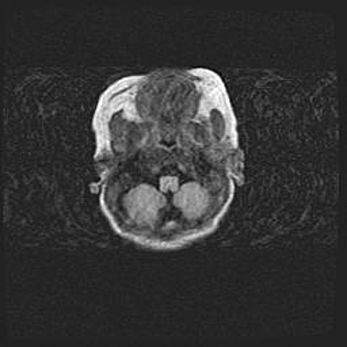

Подострая гематома правой гемисферы мозжечка.

Наружная гидроцефалия.

Возраст: 15 дней

Вес: 3100 г

Пол: женский

Окружность головы: 37 см

Срок гестации: 35-36 недель

При открытой наружной форме гидроцефалии у новорожденных расширяются и переполняются субарахноидные пространства.

Кровоизлияния в мозжечок имеют две клинико-анатомические формы: полушарные гематомы и кровоизлияния в червь.

К появлению этой патологии может привести: повреждения головного мозга, возникающие в результате асфиксии и гипоксии плода при беременности, или травмы во время родов. Редко гематома мозжечка может быть результатом первичной коагулопатии и сосудистой мальформации, диссеминированном внутрисосудистом свертывании, изоиммунной тромбоцитопении.